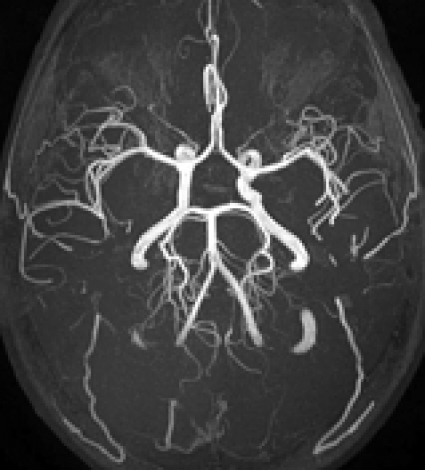

MR-angiografi. Med MR-angiografi kan man avbilda blodkärl utan kontrastinjektion eller efter intravenös kontrastinjektion. Den ovannämnda bättre undertryckningen av bakgrunden i bilden, kombinerad med ökat signal-till-brus konkurrerar med viss saturation av blod till följd av något ökad T1, men ger sammantaget bättre avbildning av små perifera kärlgrenar vid inflödes-MR-angiografi utan kontrastinjektion vid 3T [5-7] (Figur 2). Flera parametrar kan kombineras för att erhålla optimal effekt vid 3T-MR-angiografi, exempelvis kan ökat signal-till-brus användas för förbättrad upplösning, och bättre bakgrundsundertryckning kan användas för att sänka flipvinkeln i angiografisekvenser, vilket motverkar saturering av blod som flödar i bildplanet. Kombination med »magnetization transfer contrast«-teknik kan dessutom ytterligare förbättra bakgrundsundertryckningen [8]. Det är således fördelaktigt att använda en 3T-utrustning för intrakraniell MR-angiografi. Man ska dock vara medveten om att en lätt »förträngning« av arteria carotis interna vid skallbasen ibland kan ses på grund av en susceptibilitetsartefakt vid hög fältstyrka.